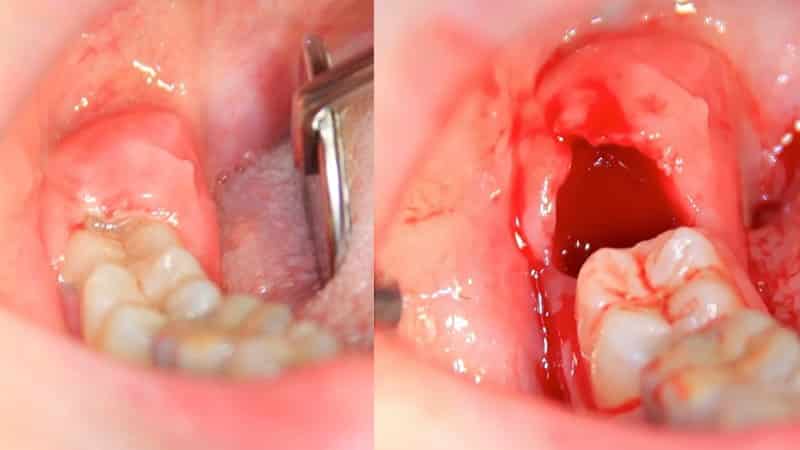

Сразу после операции образуется ямка, заполняющаяся кровью. Когда кровь сворачивается, формируется защитный барьер, представляющий собой небольшое скопление. На следующий день многие пациенты замечают пожелтение десны, что связано с образованием налета на ее поверхности после удаления. Это не является поводом для беспокойства. В течение нескольких дней этот сгусток начинает превращаться в слизистую оболочку, после чего рана полностью заживает, и дискомфорт уходит.